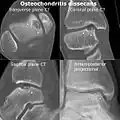

-

CT scan and projectional radiography of a case of osteochondritis dissecans of parts of the superior-medial talus.

CT scan and projectional radiography of a case of osteochondritis dissecans of parts of the superior-medial talus. -

Sagittal MRI: Linear low T1 signal at the articular surfaces of the lateral aspects of the medial condyle of the femur confirms the presence of OCD.

Sagittal MRI: Linear low T1 signal at the articular surfaces of the lateral aspects of the medial condyle of the femur confirms the presence of OCD. -